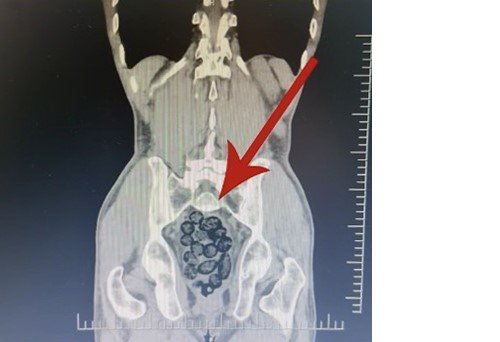

Batman’da durdurulan otobüsteki yabancı şahsın midesinden 64 parça uyuşturucu maddesi metamfetamin çıktı.

Durumundan şüphelenilen yabancı uyruklu bir yolcu üzerinde arama yapıldı. Yapılan incelemeler sonucunda yabancı uyruklu şahsın midesinde 64 Parça halinde toplam 472 gram uyuşturucu maddesi metamfetamin olduğu belirlendi.